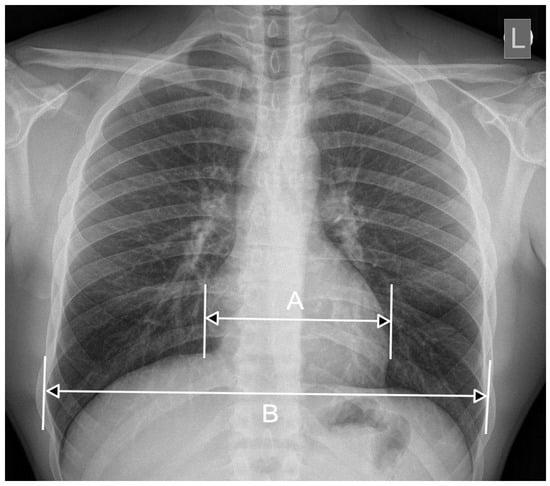

2. CTR—The Importance of Radiograph Projection